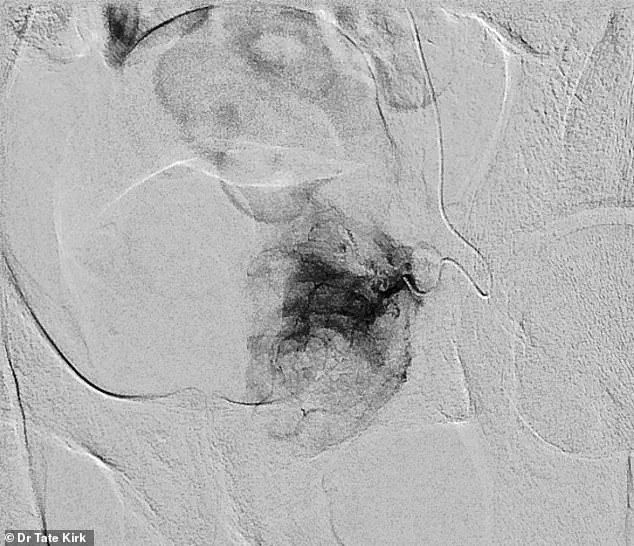

The process involves inserting a catheter into the artery supplying blood to the prostate, followed by the injection of tiny particles that block blood flow to the affected tissue.

Pre-embolization imaging reveals the artery's full vascular supply, while post-embolization scans show the complete cessation of blood flow to the prostate, effectively reducing its size and alleviating symptoms.